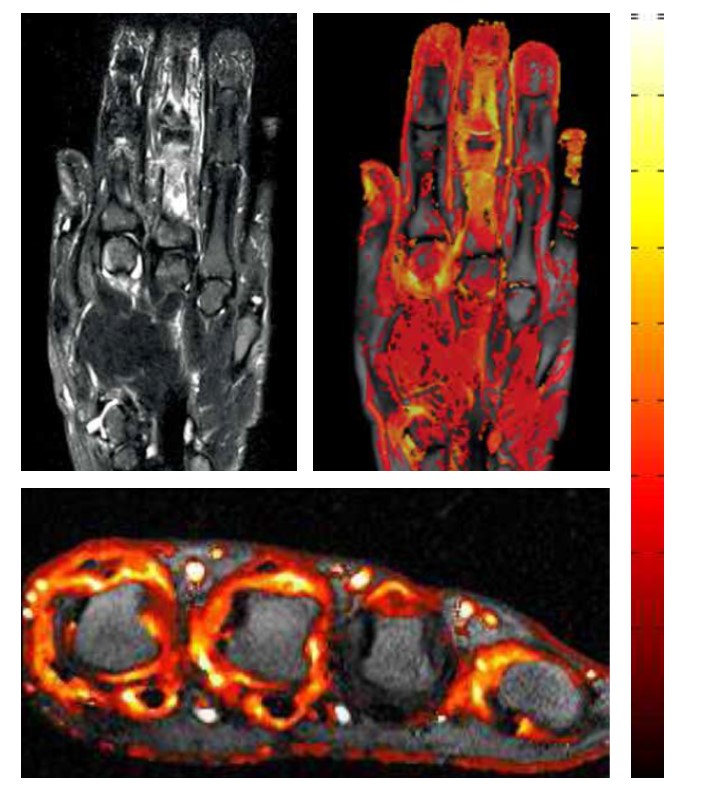

DEMRIQ

A Dynamic Contrast Enhanced MRI Quantification Method for objective assessment of treatment response in patients with Inflammatory Arthritis.